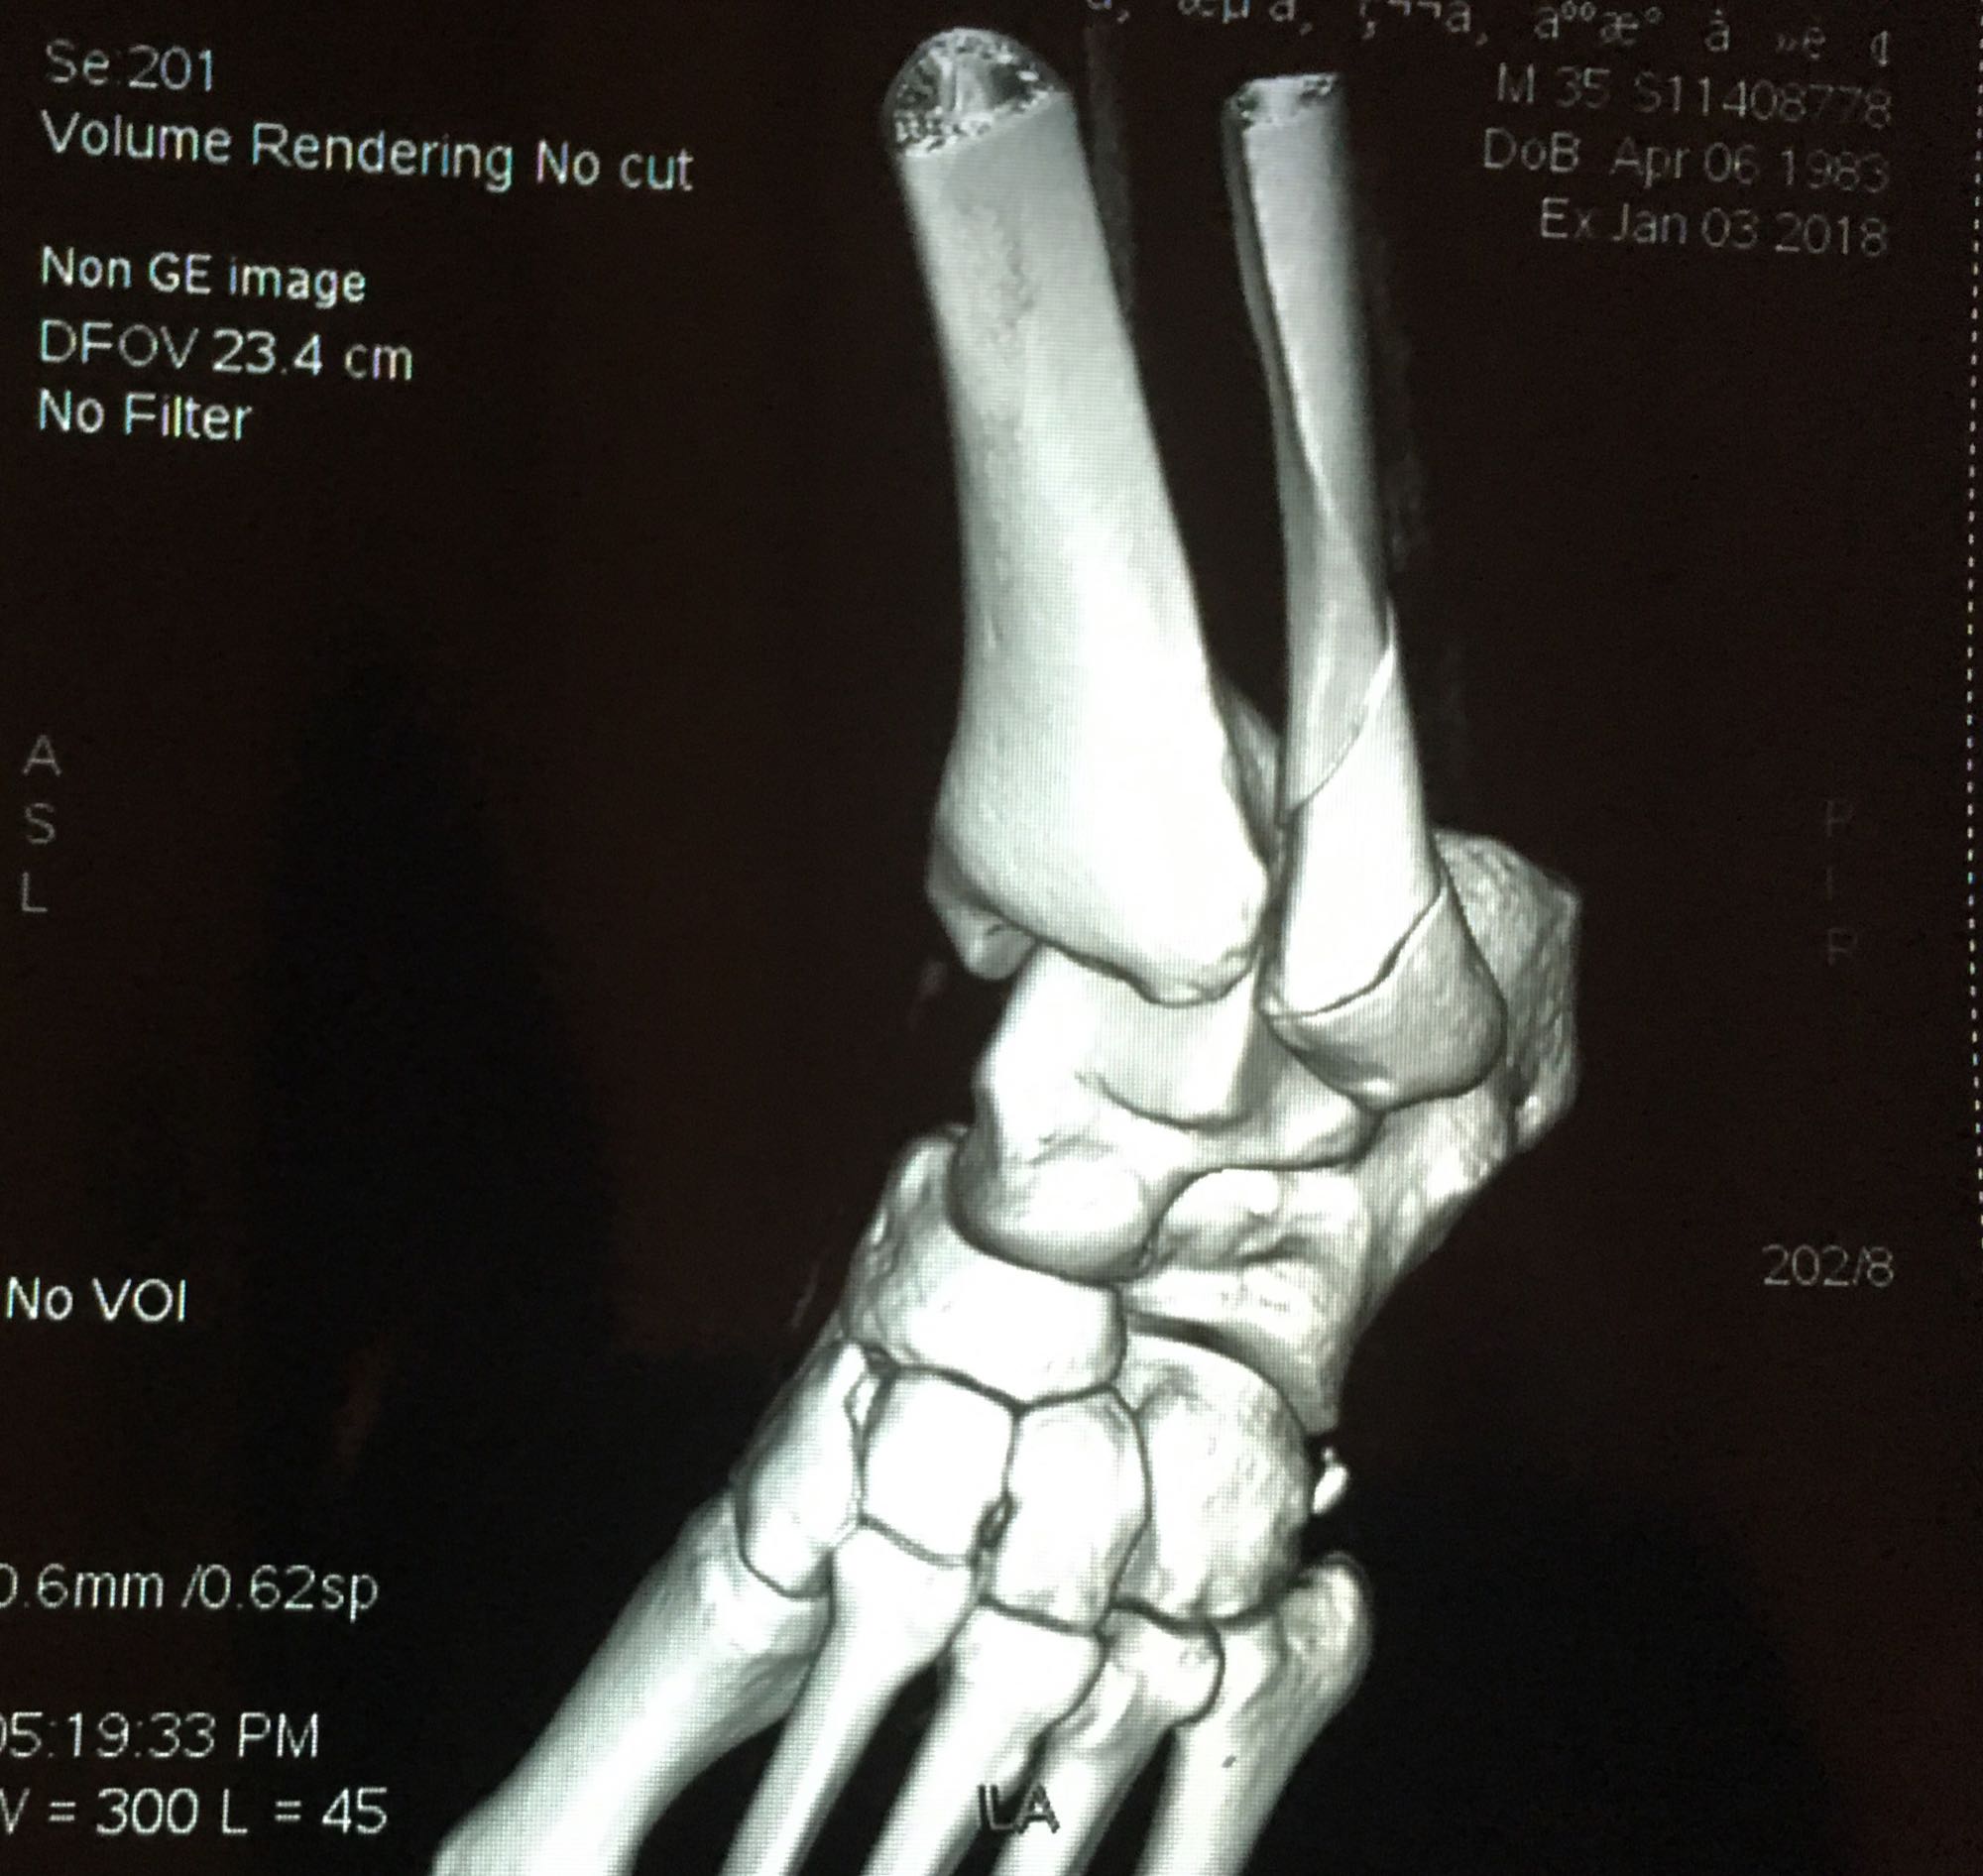

腓骨靠近踝关节处骨折,已经第七天了,西医建议手术,中医说不手

三踝骨折吧

腓骨靠近踝关节处骨折,已经第七天了,西医建议手术,中医说不手术固定好也可,迷茫中……

这个不是近关节骨折,这个是关节内骨折,关节腔肯定伤到了。手术并正确康复训练的话后遗症小,保守治疗后期康复很痛苦,同时高风险有后遗症